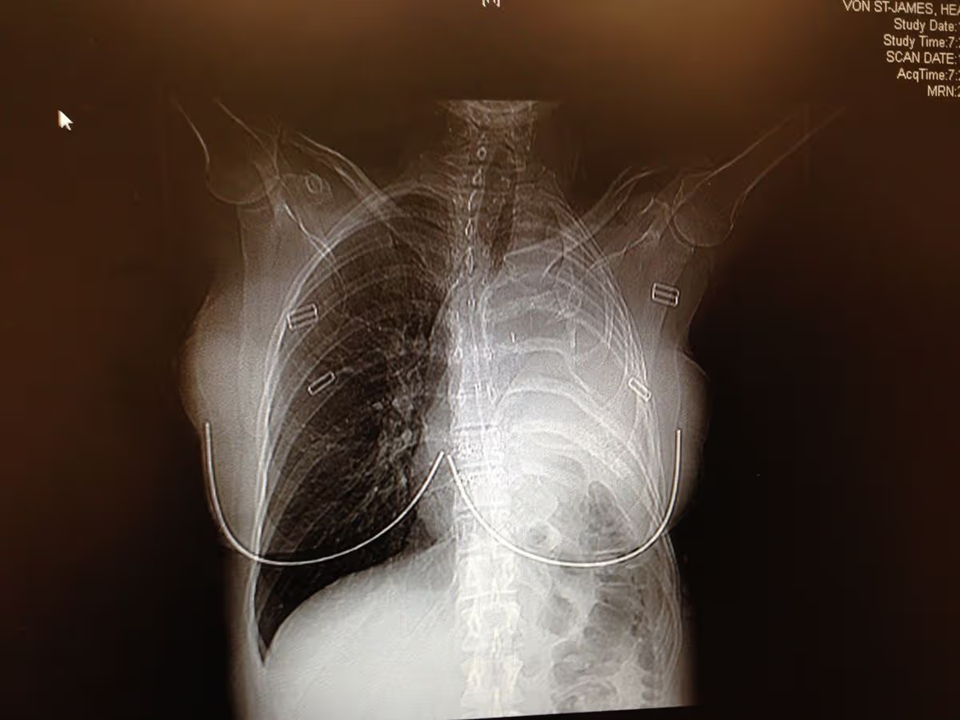

Sau nhiều thập kỷ, khi 36 tuổi và đang mang thai, Heather bắt đầu bị mệt mỏi mãn tính và sốt, phản ánh một bệnh lý tiềm ẩn. Chụp CT não và phổi cho thấy một khối u lớn và chẩn đoán cô mắc bệnh u trung biểu mô, một dạng ung thư ác tính do tiếp xúc trực tiếp với amiăng.